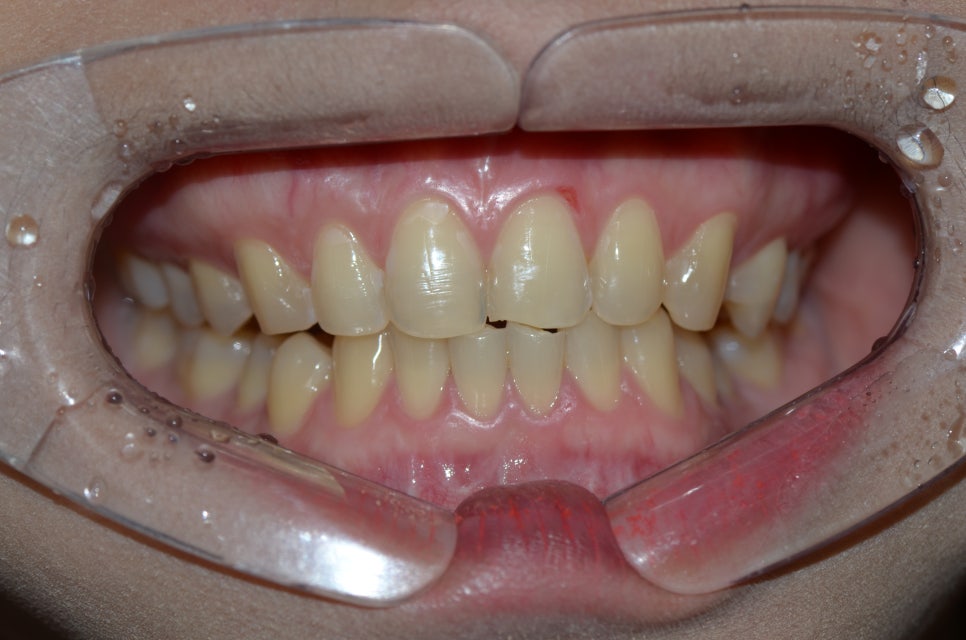

본 환자분은 노란빛이 진하게 올라오고

치아 마모가 심한편으로 안정성을 위해 지르코니아를 권유하였습니다.

본인 치아를 거울로 보았을때

치아 모서리 부분이 깨어져 나가있을 경우

힘을 많이 받고 있을 수 있습니다.